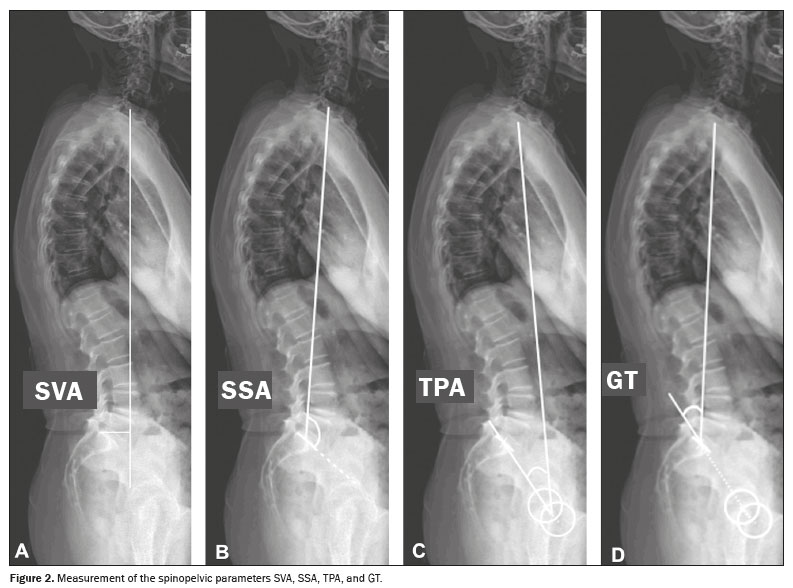

To measure the spinopelvic parameters and vertebral curvature angles, we used Surgimap software (Nemaris Inc., New York, NY, USA). The following parameters were evaluated (Figures 1 and 2): sacral slope (SS); pelvic tilt (PT); pelvic incidence (PI); lumbar lordosis (LL); thoracic kyphosis (TK); sagittal vertical axis (SVA); spinosacral angle (SSA); T1 pelvic angle (TPA); and global tilt (GT). The SS corresponds to the angle formed between the upper endplate of S1 and a horizontal line. The PT corresponds to the angle formed between a vertical line originating at the center of the femoral head and a line running from the center of the femoral head to the midpoint of the S1 endplate. The PI corresponds to the angle formed by a line running perpendicular to the sacral plateau and a line connecting its midpoint with the center of femoral rotation. The degree of LL is determined by measuring the Cobb angle from the superior endplate of S1 to the superior endplate of L1. The degree of TK is determined by measuring the Cobb angle from the inferior endplate of T12 to the superior endplate of T1. The SVA is the measurement of the horizontal distance between the plumb line of C7 and the vertical line passing through the posterosuperior point of S1. The SSA corresponds to the angle formed between the line passing from the center of C7 to the center of the endplate of S1 and the surface of the sacral endplate. The TPA corresponds to the angle formed by a line running from the geometric center of the femoral heads to the center of the T1 vertebral body and a line running from the geometric center of the femoral heads to the center of the superior endplate of S1. The GT is defined as the angle formed by a line running from the center of the superior sacral endplate to the center of the C7 vertebral body and a line running from the geometric center of the femoral heads to the center of the sacral endplate(15). The contours of the femoral heads were marked, and lines were drawn adjacent to the superior plateau of S1, superior plateau of L1, inferior plateau of T12, superior plateau of T1, and inferior plateau of C2. From those markings, the software automatically calculated the spinopelvic parameters and vertebral curvatures.